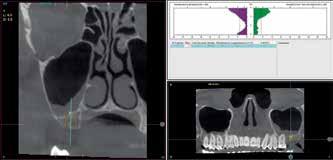

A retrospective study was carried out selecting patients with short, extra-short implants located in maxillary posterior sectors, with a bone density between 200 and 300 Hu objectified in the planning tac using the software (BTI-Scan III), in a private clinic in Vitoria, Spain, during the period from January 2017 to December 2018. Statistical data collection and analysis was performed by two different researchers. A Shapiro-Wilk test was performed on the data obtained to verify the normal distribution of the sample. The main variable evaluated was implant survival followed by crestal bone loss. Qualitative variables were described by frequency analysis. Quantitative variables were described by mean and standard deviation. Implant survival was calculated using the Kaplan method.

the residual bone (height, width, density and bone type) and the planning of the drilling to achieve three-dimensional stability of the implant and avoid micromovement in the initial phase of osseointegration9-10. In this sense, the use of implants of different diameters and lengths can provide us with a larger contact surface for osseointegration and different anchorage points that guarantee greater primary stability7,11-13 The factors that influence the achievement of primary stability in general and in these cases in particular are: geometry, length and macrodesign of the implant, drilling pattern and bone density, mainly16-18. In the present work, we show a series of cases of short (7.5 mm) and extra-short (5.5 and 6.5 mm) single-tooth implants placed in the maxillary second molar position (17 and 27), rehabilitated in a single-tooth fashion with low bone density.

A retrospective study was carried out selecting patients with short, extra-short implants located in maxillary posterior sectors, with a bone density between 200 and 300 Hu, as measured in the planning tac using the software (BTI-Scan III), in a private clinic in Vitoria, Spain, during the period from January 2017 to December 2018.

One of the main drawbacks reported in the literature is the lower predictability of these short implants when inserted in the posterior maxilla is the achievement of correct primary stability. This primary stability ensures that the newly inserted implant does not undergo micromovements during the integration phase and that the treatment is successful. To achieve this, the three-dimensional images of the cone-beam in its sectional slices allow us to choose the point of greatest density where to strategically place our anchorage zone and to individualise the drilling sequence 8-10 .

Figure 1. Initial X-ray of the case, where we can see in the second quadrant an edentulous section corresponding to tooth 27 that will be rehabilitated using dental implants.

Figure 2. Planning of the implant to be placed.

Figure 3. Post-surgical panoramic X-ray with the recently placed implant.

Figure 2 Figure 3 Figure 4 Figure 1